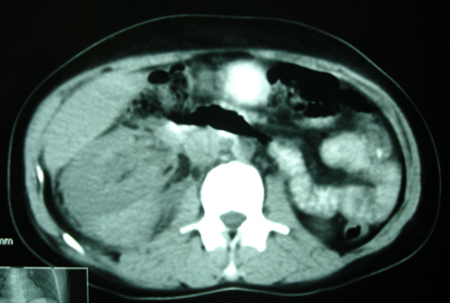

以下是引用bmw011在2009-4-23 13:28:00的发言:[br]考虑右肾包膜下血肿。

以下是引用卜一在2009-4-23 15:43:00的发言:[br]考虑右肾包膜下血肿,不排除占位病变伴出血可能,建议进一步检查。